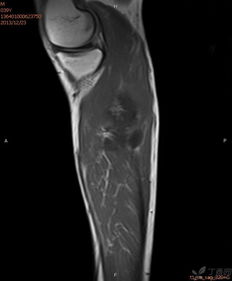

骨骼之间通过关节连接起来,使得我们的身体可以灵活地运动。关节就像是一座桥梁,连接着不同的骨骼,让它们可以相互配合,完成各种复杂的动作。关节的表面覆盖着一层软骨,这层软骨就像是一个软垫,可以减少骨骼之间的摩擦,保护关节。

软骨是一种特殊的结缔组织,它具有弹性和韧性,可以缓冲骨骼之间的冲击,保护关节。随着年龄的增长,软骨会逐渐磨损,导致关节疼痛和僵硬。因此,保持软骨的健康非常重要。

3. 关节炎:关节炎症会导致关节疼痛、僵硬和肿胀。